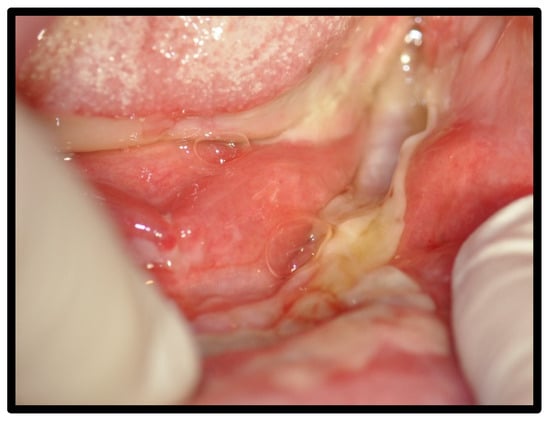

| OLP/lichenoid reaction (3 were exacerbations of previous autoimmune disease) | 12 | 50.00 | |

| Benign mucous membrane pemphigoid | 3 | 12.50 | |

| Management | Costicosteroid mouthwash, with good response | ||